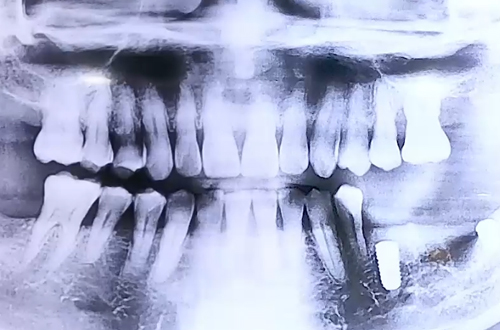

AFTER

아래 어금니의 경우 아래턱을 따라 지나가는 하치조신경과 가깝기 때문에 CT촬영을 하여 신경의 정확한 위치를 파악한 후 임플란트 진행하게 되었습니다.

치과에서 특히 아랫니 치료를 할 때에 CT촬영을 하는 이유와 그 과정, 그리고 실제 CT 사진이 어떻게 보이는지 진료일지에 담아보았습니다.